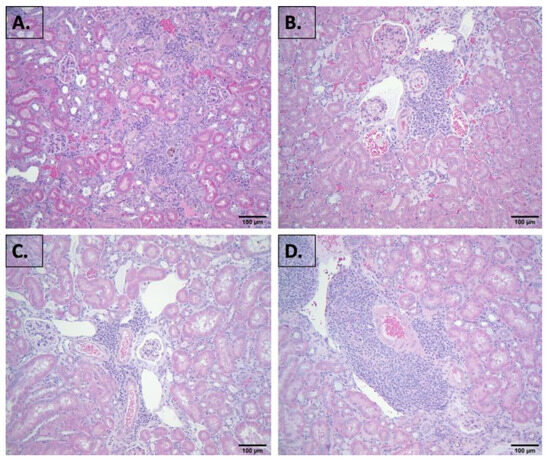

2.2. Evaluation of Blood Chemistry and Histology

4.3. Histopathological Examination of Kidney and Other Tissues